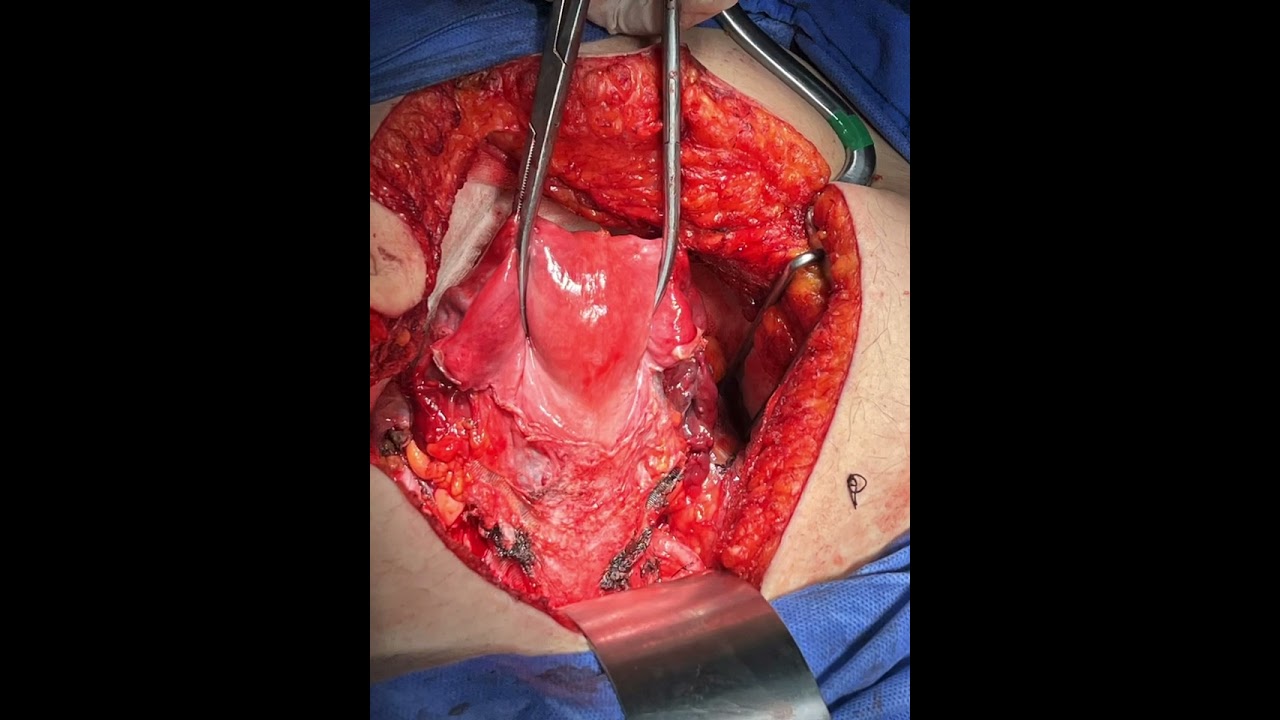

Mastectomía radical

Mastectomía radical con vaciado axilar

Tumorectomia de mama con vaciado axilar

Vaciado axilar